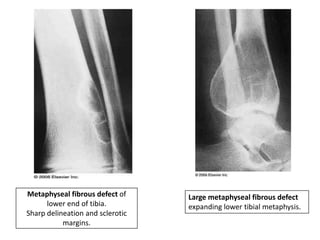

Metaphyseal fibrous defect

• It is a non-neoplastic process, possibly related to

defect in ossification.

• Occurs under the age of 10 years.

• Classically involves metaphysis in skeletally immature

individuals.

• Fibrous cortical defect- When confined to cortex.

• Lesion enlarges and extends into the adjacent

medullary cavity- Non-ossifying fibroma.

• Sites- Distal femur, proximal and distal tibia.

• Associated syndromes- Neurofibromatosis and Jaffe

Campanacci syndrome.

• Asymptomatic and are discovered incidentally.

• X ray-

• Eccentric, lytic lesion centered within the

metaphyseal cortex and adjacent medullary cavity of

long tubular bones.

• Well demarcated with sclerotic margins with internal

trabeculations.

• Trabeculations are incomplete and are the result of

scalloping of the affected cortex.

• As the patient grows, the lesion becomes

incorporated into the diaphysis.

Metaphyseal fibrous defect of

lower end of tibia.

Sharp delineation and sclerotic

margins.

Large metaphyseal fibrous defect

expanding lower tibial metaphysis.